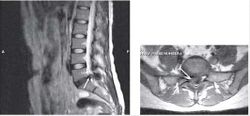

Пациентка С., 37лет, штукатур, заболела остро примерно 2 нед назад, когда утром после сна отметила острую боль при движении в шейном отделе позвоночника, ощущение скованности в шее, невозможность повернуть голову влево. В течение дня к болям в шейном отделе позвоночника постепенно присоединилась боль, иррадиирующая в левую лопатку, надплечье, по наружной поверхности левого плеча, которая имела жгучий и ломящий характер. Боль в руке и надплечье сохранялась в ночное время, нарушая сон, и частично уменьшалась в положении лежа с согнутой в локтевом суставе и заложенной за голову левой рукой. При наклоне головы в больную сторону пациентка эпизодически отмечала появление парестезий в виде «ползания мурашек» по наружной поверхности левого плеча. Прием НПВС и трамадола почти не приносил облегчения. В неврологическом статусе отмечено снижение болевой и температурной чувствительности в области левого надплечья и по наружной поверхности левого плеча, гипотония и снижение рефлекса с сухожилия двуглавой мышцы плеча слева, ограничение всех движений в шейном отделе позвоночника, но в большей степени - ротации и бокового сгибания влево. Наклон головы влево с аксиальным давлением на нее приводил к усилению боли в плече. Отмечено напряжение и умеренная болезненность при пальпации левой передней лестничной и трапециевидной мышц при отсутствии в них ТЗ. По данным рентгенографии шейного отдела позвоночника, выявлено снижение высоты межпозвоночных промежутков СIII-СIV СIV-СV, субхондральный остеосклероз, артроз дугоотростчатых суставов СIV-СV, унковертебральный неоартроз СIII-СIV СIV-СV Сагиттальный размер спинномозгового канала составил 16 мм. При МРТ шейного отдела позвоночника выявлена левосторонняя протрузия на уровне СIV-СV размером до 4,5 мм с компрессией дурального мешка, циркулярная протрузия на уровне СIII-СIV до 2 мм. Таким образом, при сопоставлении данных клинического обследования (невропатический характер болевого синдрома, наличие характерных для поражения корешка С5 чувствительных, двигательных и рефлекторных нарушений) с данными рентгенографии и МРТ позвоночника - наличие на соответствующем уровне (СIV-СV) латеральной протрузии и дистрофических изменений дугоотростчатого сустава с формированием сужения левого корешкового отверстия - у пациентки можно диагностировать компрессионную радикулопатию корешка СV слева, обусловленную левосторонней грыжей диска СIV-СV на фоне первично узкого спинномозгового канала на шейном уровне (Рис. 2). ЭМГ-обследование не проводили из-за небольшой (менее 3 нед) длительности заболевания и дальнейшей его положительной динамики на фоне лечения. Пациентке были назначены венотонические препараты (эскузан по 15 капель 3 раза в сутки), амитриптилин в дозе 50 мг/сут, внутривенные инфузии пентоксифиллина (5 мл 2% раствора), массаж мышц левой руки и надплечья, мануальная терапия (мобилизация шейных и грудных ПДС), ПИР трапециевидной и лестничной мышцы. На 10-е сутки лечения болевой синдром значительно уменьшился, его полный регресс произошел через 1,5 мес после начала заболевания.